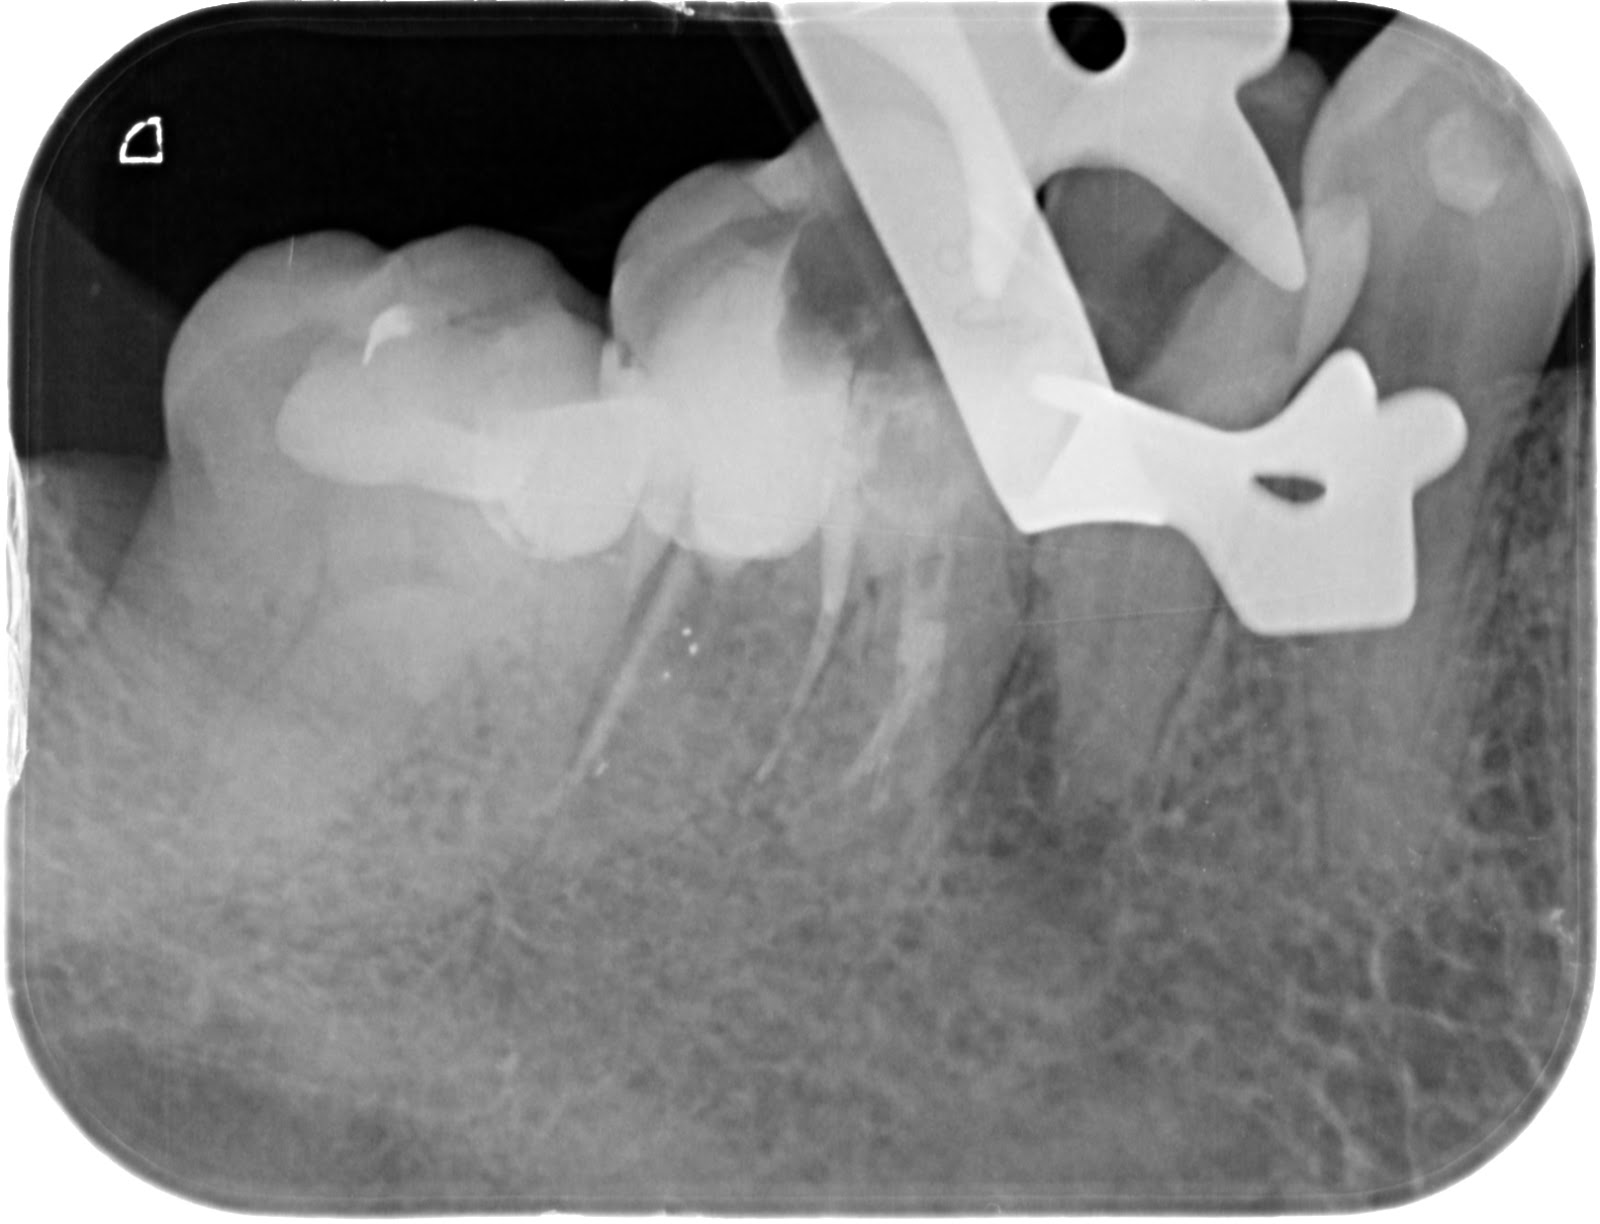

En la radiografía se observa

que tiene una endodoncia deficiente en el 45 con imagen radiográfica

periapical. Se decide no tocar el 46 ya que no tiene sintomatología ni signos

radiográficos.

Morita a 19 mm y confirmamos con una radiografía